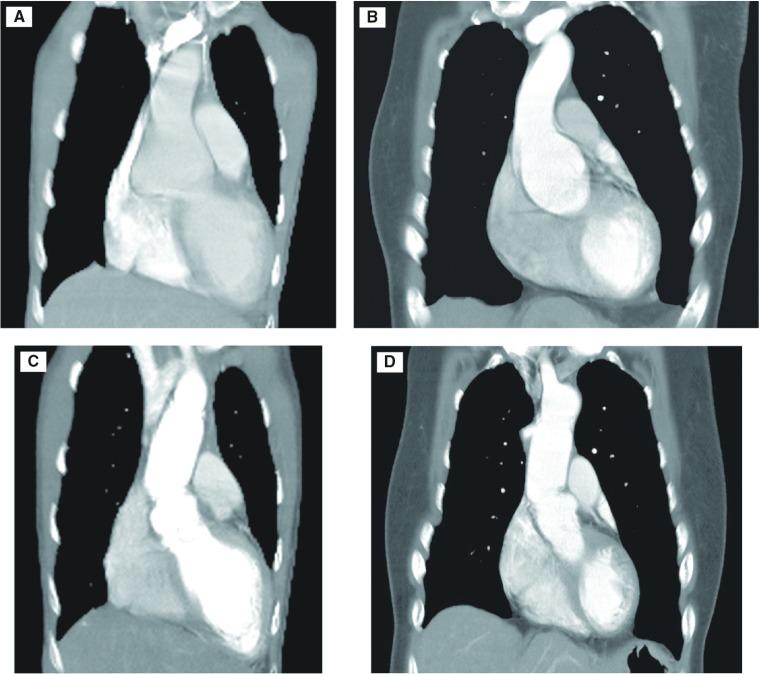

马凡综合征保留主动脉瓣手术中的改良袖状技术

Modified Sleeve Technique in Aortic Valve-Sparing Operation for Marfan Syndrome.

We devised a simple modification of the Florida Sleeve procedure to perform aortic valve-sparing surgery. This technique is simple, quick, effective, and safe. We used this technique in operations performed on two young patients with Marfan syndrome. The initial and short-term results were satisfactory.

摘要

我们设计了一种对佛罗里达套管手术的简单改良方法来实施保留主动脉瓣的手术。该技术简单、快速、有效且安全。我们在两名患有马凡综合征的年轻患者的手术中使用了此技术。初期和短期结果令人满意。